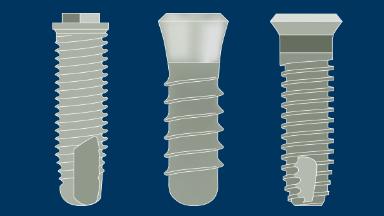

The scientifically documented success of implants has led to the development of many different implant designs, materials, surface technologies, and surgical methods.

Numerous companies manufacture and market implant systems, and most of these systems include implants of more than one design.

At present there are well over 2,000 different implant designs available worldwide. Moreover, some of these systems include prosthetic components designed to be compatible only with implants from the same manufacturer.